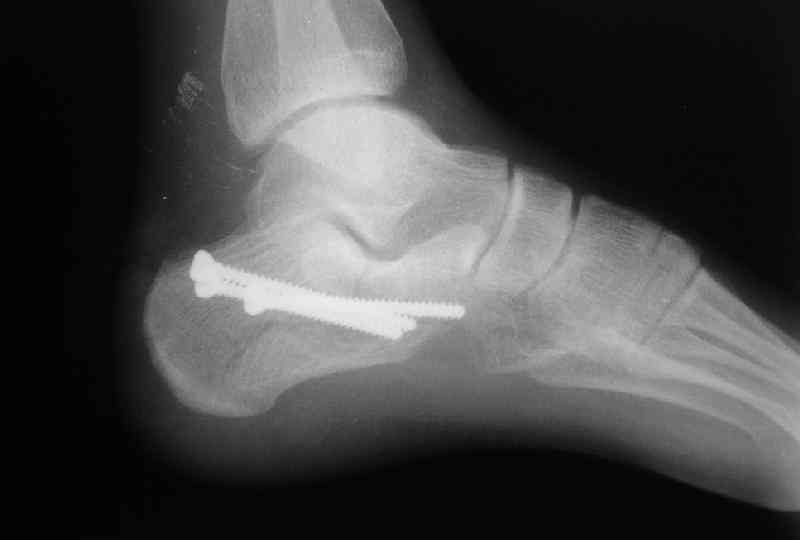

Открытый и закрытый способы лечения.